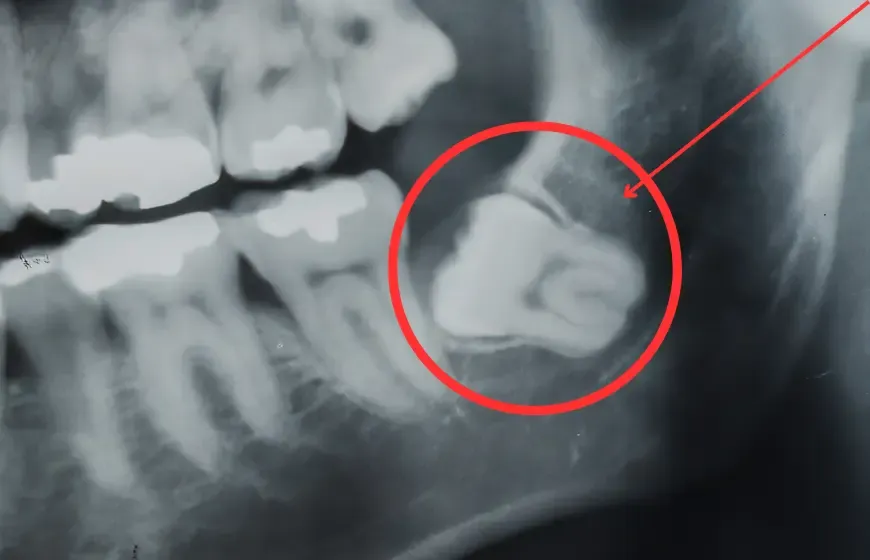

Zęby mądrości, czyli ósemki, to ostatni etap kształtowania się uzębienia. Wyrzynają się one najpóźniej, zazwyczaj między 17. a 25. rokiem życia, choć u wielu osób nie pojawiają się wcale lub pozostają zatrzymane w kości szczęki. Ich pojawienie się często wiąże się z różnego rodzaju komplikacjami, które mogą być uciążliwe i wymagać interwencji stomatologicznej.

- Brak miejsca w łuku zębowym: Ósemki często wyrzynają się pod nieprawidłowym kątem lub nie mają wystarczająco miejsca, co prowadzi do bólu i może wpływać na ustawienie pozostałych zębów.